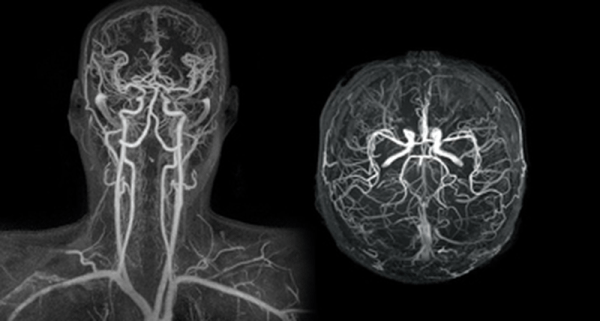

Μαγνητική Αγγειογραφία (MRA)

Η Μαγνητική Αγγειογραφία (MRA) είναι μια μη επεμβατική εξέταση που χρησιμοποιεί τη μαγνητική τεχνολογία και τους υπολογιστές για να δημιουργήσει λεπτομερείς εικόνες των αγγείων στο εσωτερικό του σώματος, συμπεριλαμβανομένων των αρτηριών και των φλεβών.